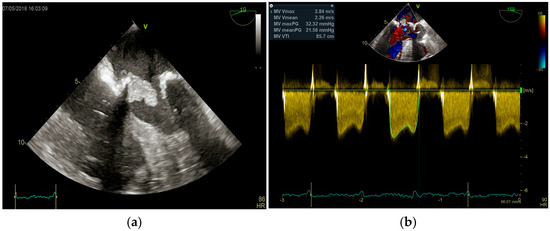

Multimodality Imaging in Infective Endocarditis: A Clinical Approach to Diagnosis

by Leonardo Brugiatelli, Francesca Patani, Carla Lofiego, Martina Benedetti, Irene Capodaglio, Pongetti Giulia, Francioni Matteo, Paolini Enrico, Nazziconi Marco, Kevin Maurizi, Furlani Giulia, Massari Arianna, Luciani Simone, Anselmi Benedetta, Gatti Chiara, Schicchi Nicolò, Fogante Marco, Tarsi Giovanni, Dello Russo Antonio, Di Eusanio Marco, Marini Marco and Fabio Vagnarelliadd Show full author list remove Hide full author list

Medicina 2025, 61(12), 2241; https://doi.org/10.3390/medicina61122241 - 18 Dec 2025

Infective endocarditis (IE) is a life-threatening condition with a rising incidence, demanding rapid and precise diagnosis. While echocardiography remains the cornerstone of initial evaluation, its limitations in complex cases—such as those involving prosthetic valves or cardiac devices—are well-known. This review synthesizes current evidence [...] Read more.

Infective endocarditis (IE) is a life-threatening condition with a rising incidence, demanding rapid and precise diagnosis. While echocardiography remains the cornerstone of initial evaluation, its limitations in complex cases—such as those involving prosthetic valves or cardiac devices—are well-known. This review synthesizes current evidence and guidelines to outline a practical, multimodality imaging approach for IE. We emphasize that integrating advanced techniques like cardiac computed tomography (CT) and [18F]-fluorodeoxyglucose positron emission tomography/computed tomography (FDG PET/CT) early in the diagnostic pathway, particularly in high-risk scenarios, significantly enhances diagnostic certainty, guides therapeutic decisions, and improves patient outcomes. A tailored imaging strategy, driven by clinical presentation and integrated within a multidisciplinary endocarditis team, is paramount for modern IE management. Full article

(This article belongs to the Special Issue Diagnosis and Treatment of Valvular Heart Diseases)

Show Figures

Figure 1